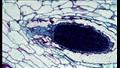

ويُعرف انخفاض عدد الحيوانات المنوية، والذي يُطلق عليه طبيا قلة النطاف، بوجود أقل من 15 مليون حيوان منوي في 1 ملليلتر من السائل المنوي. ويسمى عدم وجود حيوانات منوية في السائل المنوي بـ"فقد النطاف".